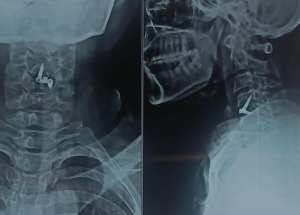

Expert spine services including minimally invasive surgery, pain management, and deformity correction.